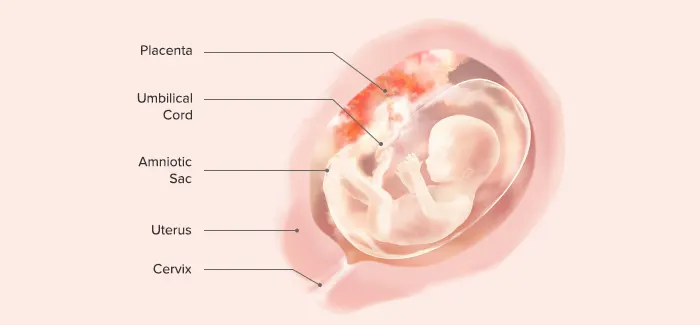

III. End of 12th Gestational Week (First Trimester)

Length: 7–8 cm

Weight: 45 g

Nail beds are forming on fingers and toes.

Spontaneous movements are possible, although they are usually too faint to be felt by the mother.

Some reflexes, such as the Babinski reflex, are present.

Bone ossification centers begin to form.

Tooth buds are present.

Sex is distinguishable by outward appearance.

Urine secretion begins but may not yet be evident in amniotic fluid.

The heartbeat is audible through Doppler technology.